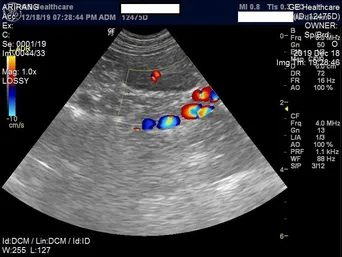

Echocardiography: Ultrasound of the heart

In order to be able to evaluate the inner workings of the heart in detail we offer echocardiography.